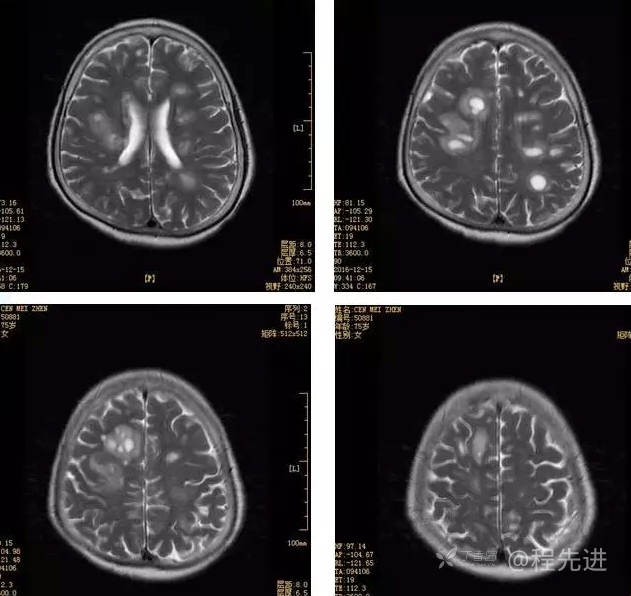

3月特别精彩病例|头晕伴左侧肢体乏力、行走不稳1周【结果已公布】

患者性别:女

患者年龄:75岁

简要病史:头晕伴左侧肢体乏力、行走不稳1周。否认高血压、脑梗塞、肝炎、糖尿病、肺结核病史。否认疫区疫水接触史。